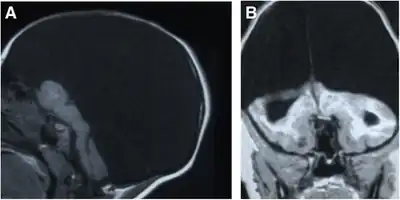

| a,b)MRI performed on individual affected by hydranencephaly | |